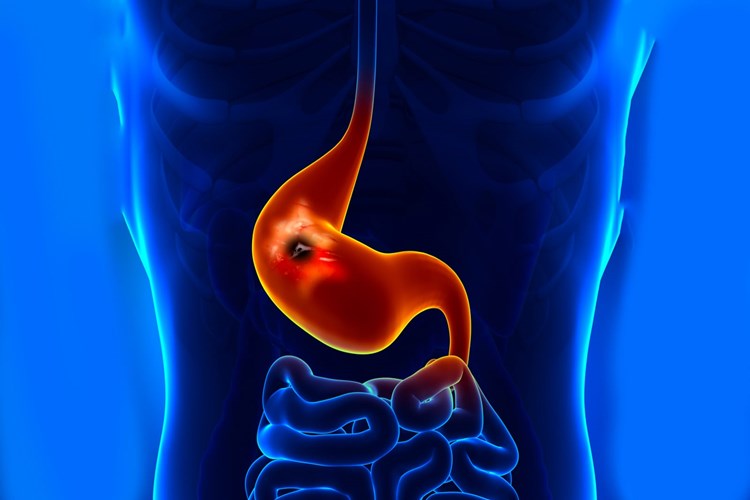

Pankreatit, akut veya kronik olarak iki ana türde

görülebilen pankreas iltihabıdır. Pankreatitin bazı nedenleri genetik

faktörlere dayanabilir, ancak bu durumlar genellikle nadirdir. Genetik

pankreatit, aile geçmişi ile ilişkilendirilen ve belirli genetik mutasyonlarla

ilişkilendirilen bir durumdur. Bu mutasyonlar, pankreasın normal işlevini

etkileyebilir ve pankreatitin riskini artırabilir. Özellikle aile geçmişi

içinde pankreatit öyküsü bulunan kişilerde genetik faktörler daha fazla önem

kazanabilir.

Pankreatitin ana nedenleri arasında alkol kökenli, safra

taşı, yüksek trigliserid seviyeleri ve bazen ilaçlar yer alır. Ancak bu

nedenlerin çoğu genetik faktörlerden ziyade yaşam tarzı ve çevresel etmenlerle

ilişkilidir.

Eğer ailenizde pankreatit öyküsü varsa veya pankreatit

riskinizi değerlendirmek istiyorsanız, bir genetik danışman veya uzman, genetik

testler ve aile geçmişi analizi ile size daha fazla bilgi sağlayabilir.

Unutmayın ki pankreatit genetik faktörlerle ilişkilendirilse de, birçok

pankreatit vakası yaşam tarzı ve çevresel etkenlere bağlıdır, bu nedenle

sağlıklı yaşam tarzı tercihleri ve risk faktörlerinin azaltılması pankreatit

riskini azaltabilir.